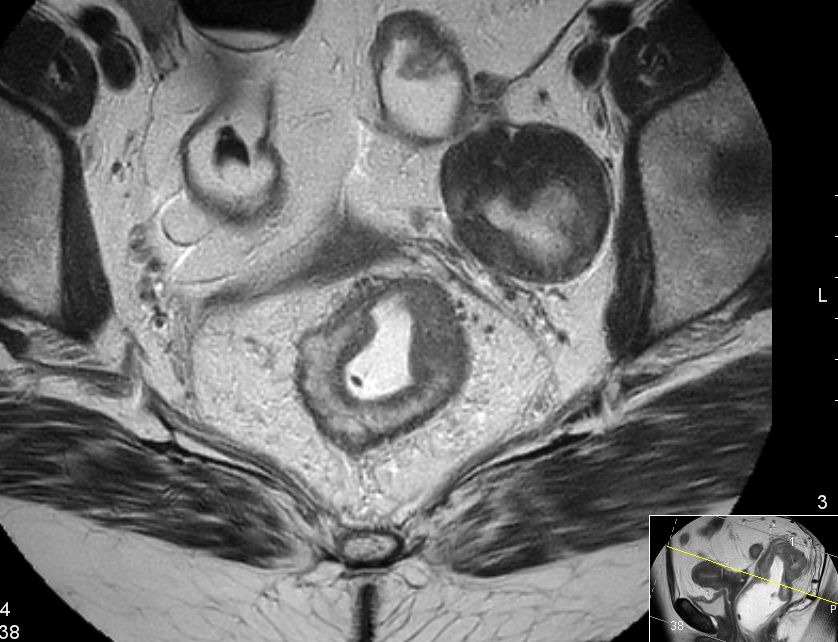

Eingelagert einzelne Gefäße. Angrenzendes Ovarialparenchym komprimiert und mit mehreren Corpora albicantia. MRT sT1W TSE![]() |

MRT sT2W TSE![]() | |||